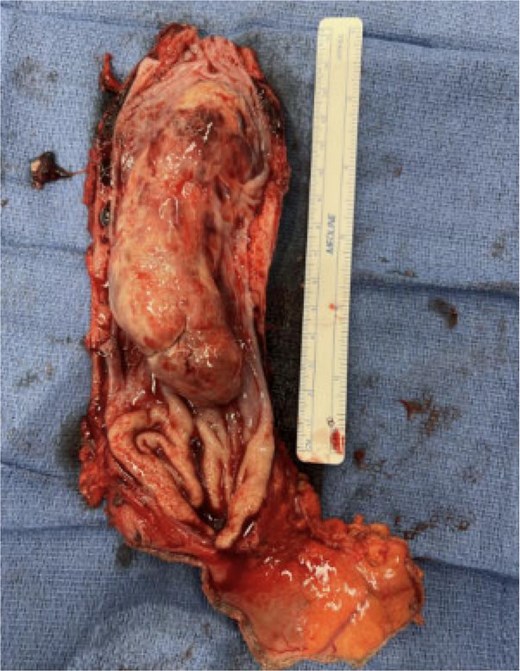

A multidisciplinary discussion was held and in the setting of the rapid tumor progression with biology favoring sarcoma and no evidence of distant disease, the decision was made to pursue upfront surgical resection rather than neoadjuvant therapy. The patient underwent a three field near total esophagectomy with an uneventful postoperative hospital course. A fluoroscopic esophagram was performed on postoperative day 6 without evidence of contrast extravasation (Fig. 4). The final pathology revealed an 8.7 cm high-grade pleomorphic rhabdomyosarcoma with mucosal and submucosal invasion, sparing the muscularis propria with 0/11 lymph node involvement (Fig. 5). This was formally graded as Stage IIIA (pT2N0M0), based on the soft tissue sarcoma criteria of AJCC.

Fluoroscopic esophagram showing an intact anastomosis without contrast extravasation on postoperative day 6 status post-esophagectomy.